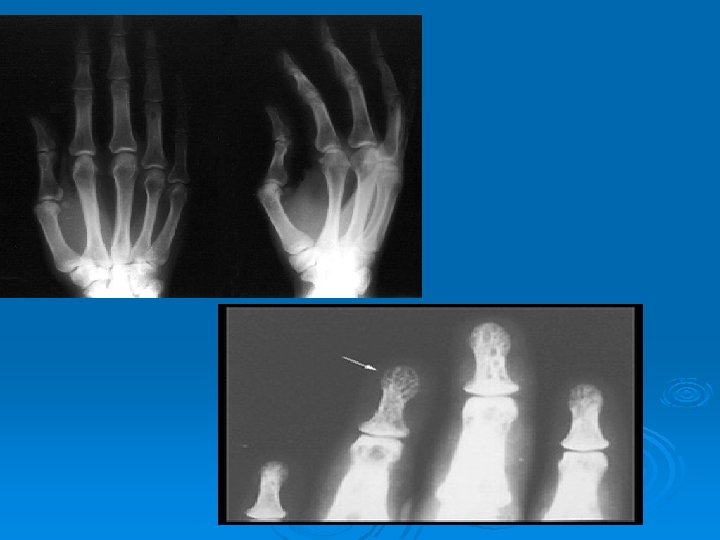

ELDE LİTİK LEZYONLAR

Prognoz • İyi: Erythema nodosum, akut inflammatuar bulgular (ateş, polyarthritis). • Kötü: Lupus pernio, kronik uveitis, yaş >40, kronik hypercalcemia, nephrocalcinosis, siyah ırk, nasal mucosal tutulum, kistik kemik lezyonları, neurosarcoidosis, myokardial tutulum.